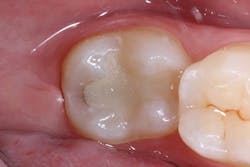

A 26-year-old patient visited a private office for a regular dental checkup. The clinical evaluation showed a No. 18 Class I composite restoration with marginal leakage and infiltration on the distal side of the cavity (figure 1). The surface of the restoration was irregular and lacked dental anatomy. Due to the patient’s esthetic needs and the remaining amount of natural tooth structure, composite filling was selected for the restoration.

The surface anatomy of the restoration was also compromised.